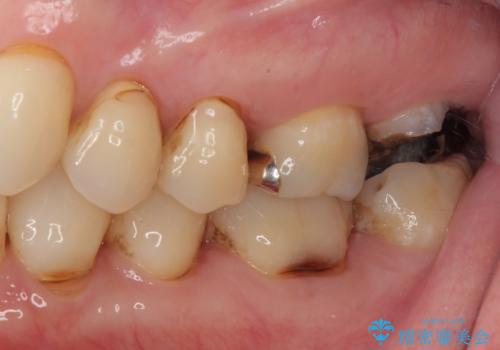

- 上の奥歯を放置してしまったとのことで来院された患者様です。

虫歯が大きいのでクラウンによる治療が必要となりますが、咬む力がとても強いために、歯と同じ堅さであるPGAクラウン(白金加金合金クラウン)をお勧めしました。

上の奥歯であることから、審美性よりも機能性を優先され、ゴールドクラウンを選択されました。